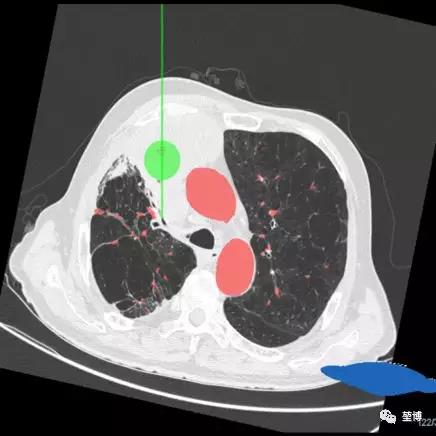

患者病灶位于右上叶前段,病灶大小约77mm*67mm*59mm,病灶较大,由于患者已是癌症晚期,出现多发转移,不具备手术指征,因此考虑姑息性治疗。龙主任结合病情拟LungPro导航引导下行BTPNA肺部肿瘤微创介入治疗——激光消融治疗。

术前路径规划

一、气道内消融路径规划

二、气道外消融路径规划

POE穿刺点位于RB3

建立隧道直达病灶中心